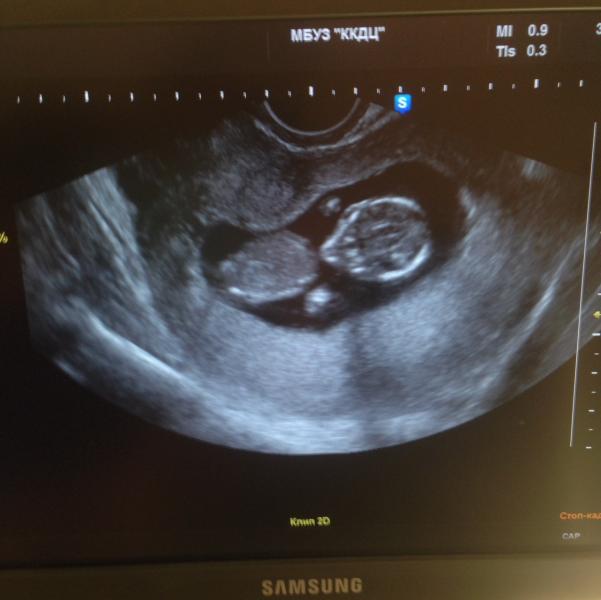

Ну вот и первый скрининг позади! Все хорошо, слава богу🙏 больше переживала🙈 Теперь расскажу немного о впечатлениях и нашем диагностическом центре. Очередь живая, но продвигается довольно таки быстро. Врач не распинается, сказала, что все хорошо и на этом хватит. Кроху нашу показывать мне до последнего не хотела, но все таки видимо "сжалилась" на до мной и разрешила сделать снимок с монитора на телефон. Мужа конечно же не пустили! Но хоть и на этом спасибо) В принципе от бесплатной диагностики я большего и не ожидала! Сейчас в ближайшее время планируем с мужем сходить к Александрову. Уж очень хочется рассмотреть нашего малыша и конечно любопытство не даёт покоя, кто же там))) Девочки, только вот скажут ли нам пол малыша на 15 неделе? Вроде в ожидании третьего, а все, как в первый раз)))) раньше наверное не такая любопытная была🙉 А это наша кроха, как же мы ее любим❤️❤️❤️